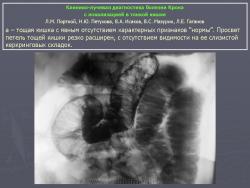

В дифференциально-диагностическом плане интересно -